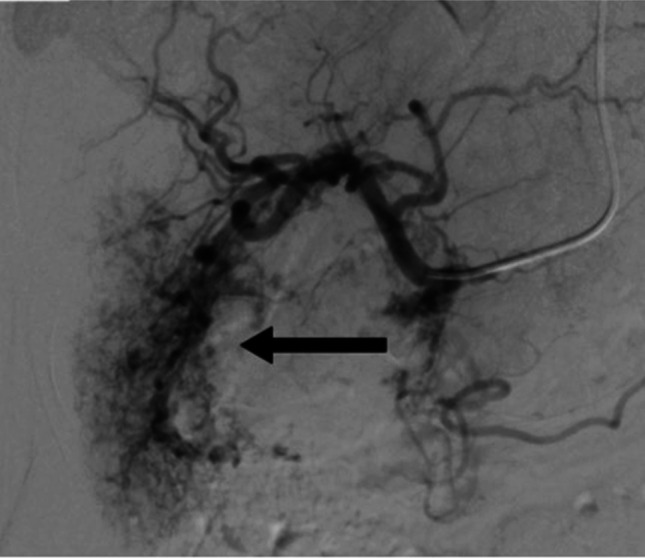

Symptomatic hepatic hemangiomas are commonly treated by transcatheter arterial embolization as an alternative to surgical resection. Bile duct complications are rare. An 80-year-old woman had a progressive refractory stricture postbleomycin transcatheter arterial chemoembolization. Magnetic resonance cholangiopancreatography showed that the hemangioma reduced in size, but there was a new 2 cm hilar stricture on cholangiopancreatography. Digital cholangioscopy and biopsy showed benign changes. Despite repeat dilations and stent treatments, she had persistent stricture and recurrent cholangitis. The stricture was not operable. The stricture was likely from angiosclerotic effects of bleomycin. The bile duct is prone to ischemic injury as it lacks dual blood supply.